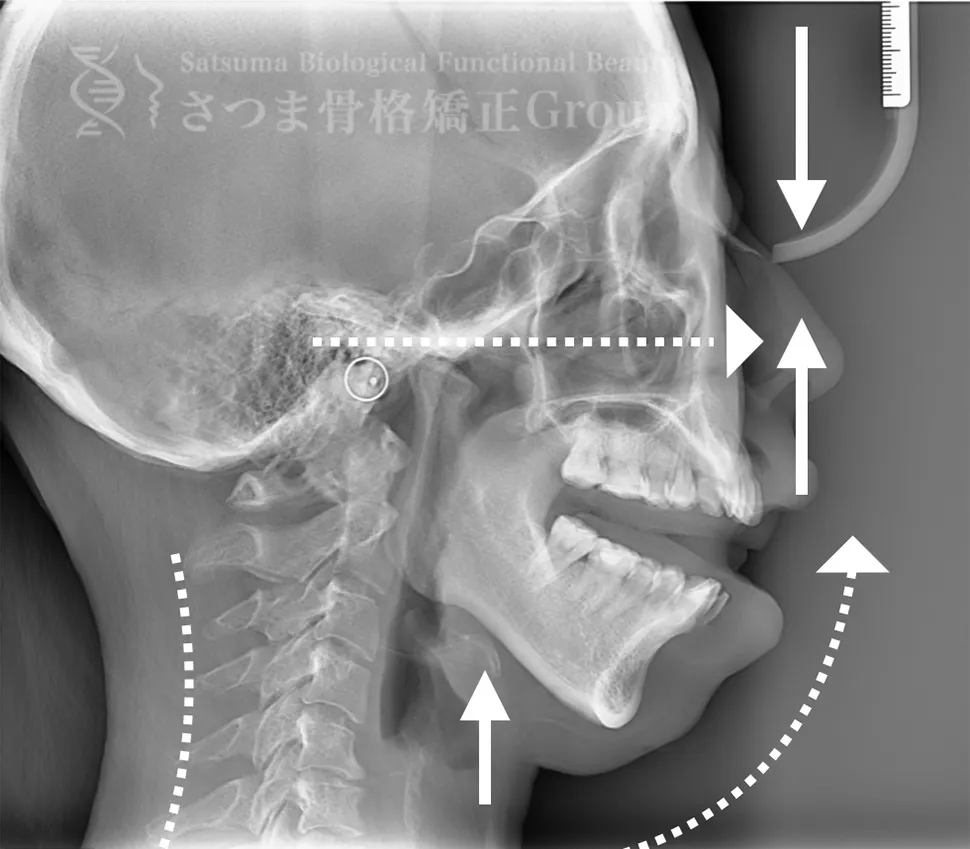

口蓋骨の下方変位 下顎位の滑落 ストレートネック 中顔面と人中が伸びて見える

Inferior displacement of the palatine bone Sagging of the mandibular position Straight neck The midface and philtrum appear elongated

AFTER

口蓋骨を上方に整復 下顎位が上がる ストレートネックの改善 中顔面と人中が短縮し小顔に見える

Repositioning the palatine bone upward The mandibular position is elevated Improvement of straight neck The midface and philtrum are shortened, giving the appearance of a smaller face